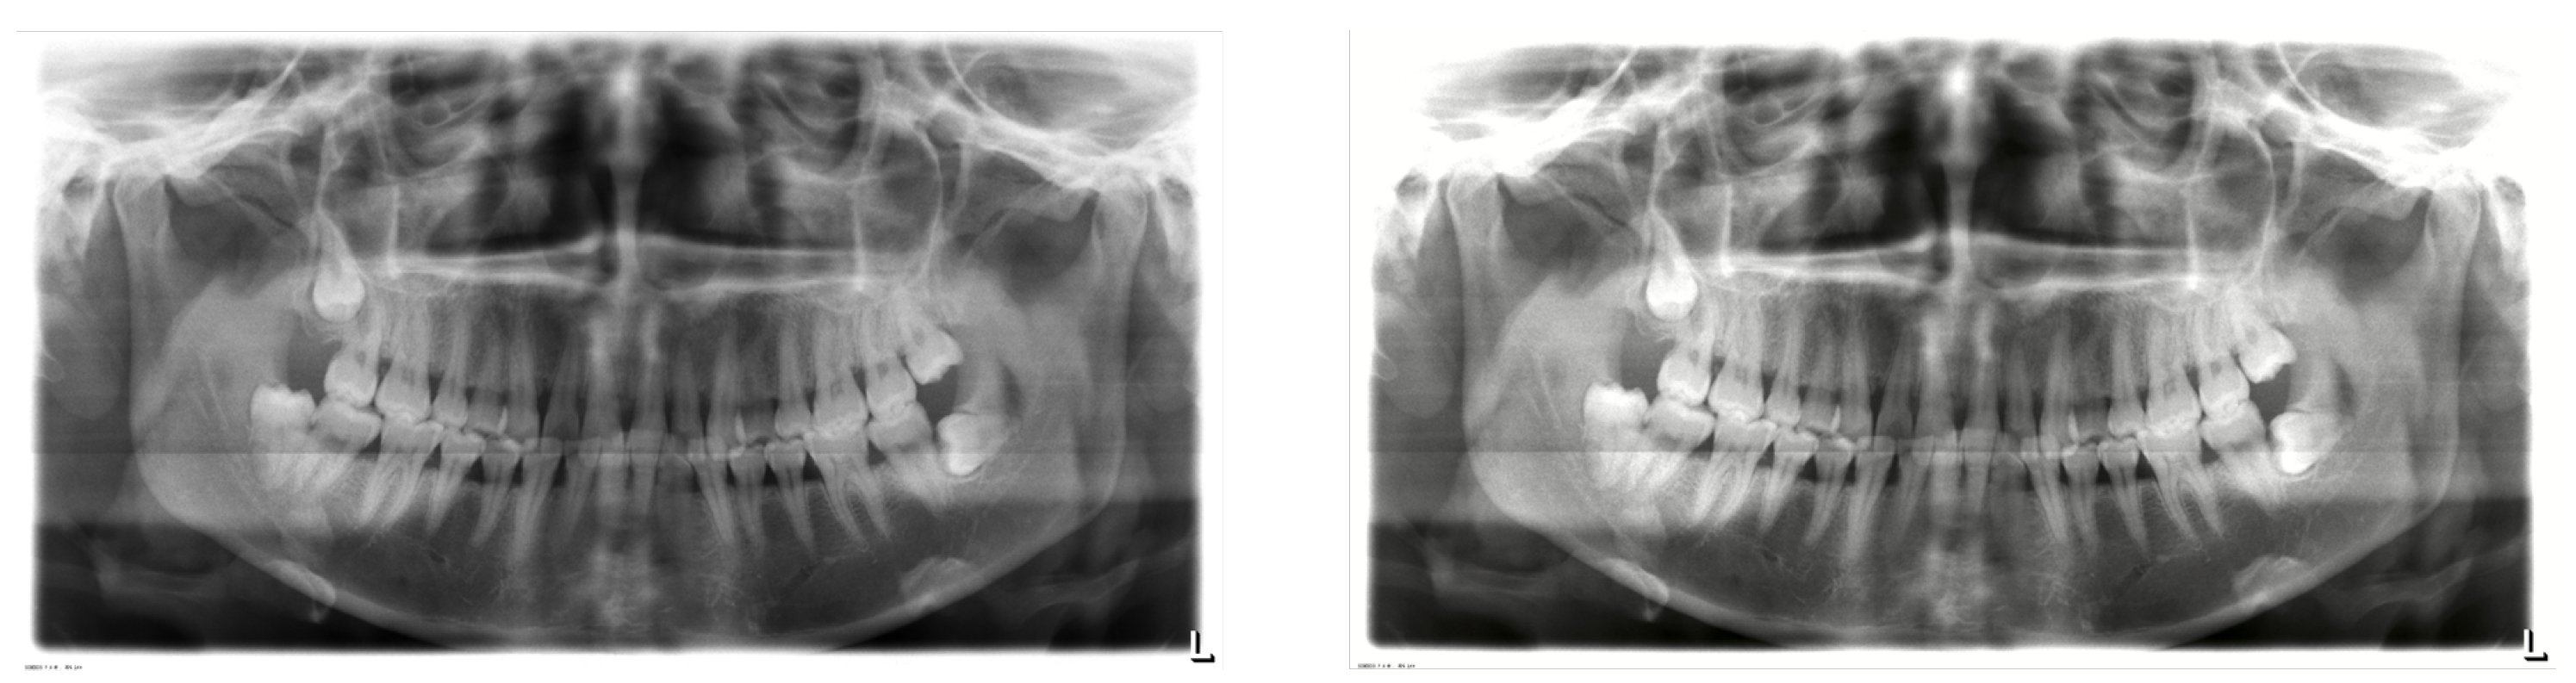

6.6. Visualization Results